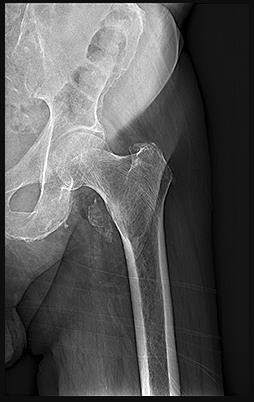

Question 2:

A 12-year-old boy presents with left thigh pain, an antalgic gait, and an externally rotated left lower extremity. Radiographs demonstrate the pathology shown. Which of the following is considered an absolute indication for prophylactic pinning of the asymptomatic, contralateral hip in a patient presenting with Slipped Capital Femoral Epiphysis (SCFE)?

Correct Answer: Underlying endocrine disorder (e.g., hypothyroidism)

Explanation:

SCFE is characterized by a displacement of the proximal femoral epiphysis. Prophylactic pinning of the contralateral hip is somewhat controversial but generally recommended in patients with a high risk of subsequent contralateral slip. Absolute indications or highly strong recommendations for prophylactic contralateral pinning include an underlying endocrine disorder (such as hypothyroidism or growth hormone deficiency), renal osteodystrophy, previous radiation therapy, and presentation at a very young age (e.g., < 10 years). Endocrine disorders dramatically increase the risk of bilateral involvement, often occurring simultaneously or sequentially.